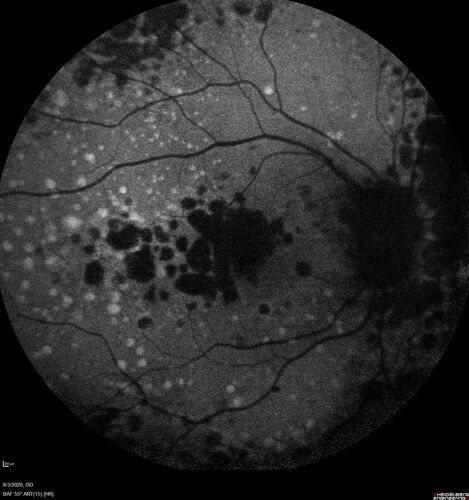

Dry AMD geographic atrophy and cystoid macular edema

79 year old vision is in for a checkup with no visual complaints in the left eye.  This is her better eye.  VA 20/200 OD, 20/50 OS.  3 years ago she had a CRVO in the left eye.  She is also diabetic for 20 years, has carotid insufficiency and anemia.  Left eye shows CME.  This was not treated and the vision improved to 20/40 over the next year although mild edema persisted.